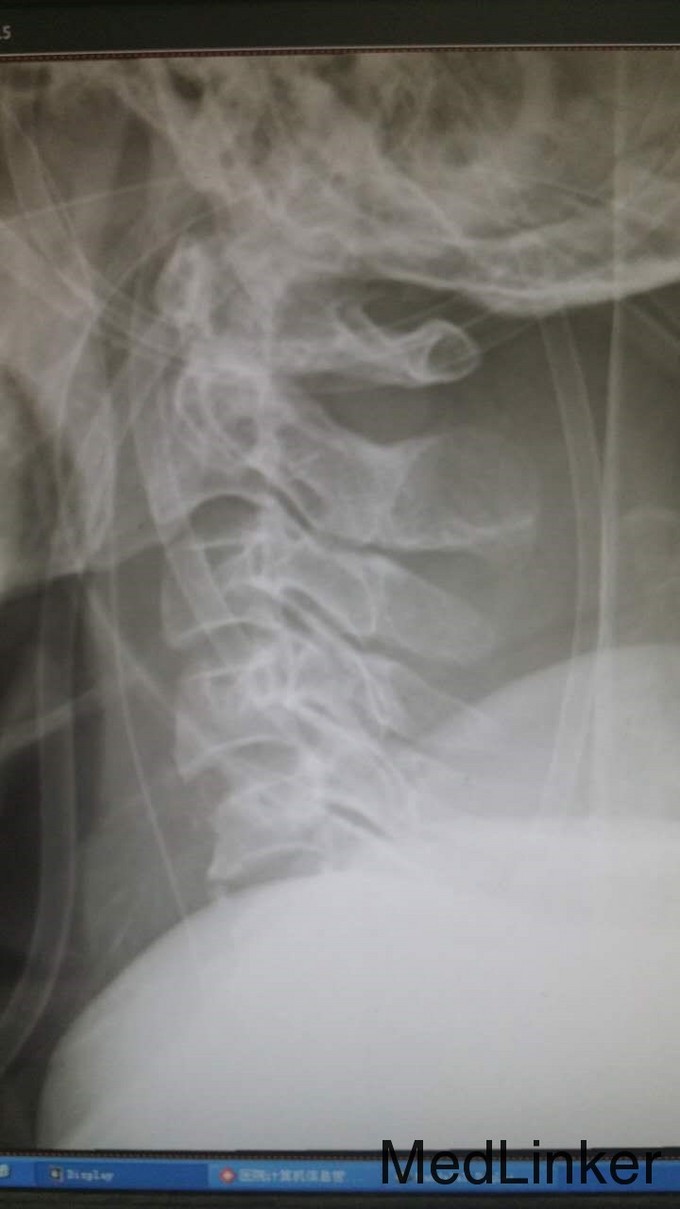

查体:T4平面以下痛觉消失,四肢肌力0级。双侧病理征阳性。 辅检:全身CT示:C4左侧椎扳、侧块、C5-6左侧横突多发骨折,C5椎体压缩骨折,C4椎体滑脱,颅内未见明显血肿,胸腹盆末见明显外伤行病变。头颅MRI示:C3-6水平颈髓出血伴水肿。

诊断:1.C3-6水平颈髓损伤出血伴水肿,2.C4左侧椎扳、侧块、C5-6左侧横突多发骨折,3.C5椎体压缩骨折,4.C4椎体滑脱(Ⅰ度) 治疗:伤后5天,予行C3-6椎板切除、椎管减压,侧块固定融合术